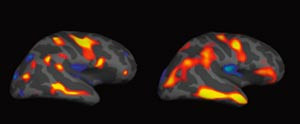

En gruppe forskere ved NTNU har ved hjelp av en ny MR-metode studert hjernens strukturer ved 15 års alder hos en gruppe premature med fødselsvekt < 1 500 g og sammenliknet dem med ungdommer som var små ved termin og en gruppe normale (1). Alle barn er fulgt prospektivt siden fødselen ved St. Olavs Hospital.

Utgangspunktet var at den affiserte hjerneutvikling som kan ses hos premature, kan ha negative følger for barnets senere utvikling. I studien ble MR gjennomført ved hjelp av en ny automatisert teknikk, etterfulgt av morfometriske analyser. Metoden omfatter målinger av hjernebarkens tykkelse, areal og volum for hvert enkelt individ og sammenlikner hjernens anatomi på tvers av gruppene.

Det ble påvist strukturelle forskjeller mellom prematurgruppen og de andre mht. kortikal overflate, areal og volum og forskjellene var størst for de minste og mest premature. Blant premature var det en sammenheng mellom både overflateareal og kortikalt volum og målt IQ. Mengden grå substans i forhold til hjernens totale volum var lavere hos de premature sammenliknet med kontrollpersonene.

Forfatterne mener at den nye MR-metoden gjør det mulig å studere sammenhenger mellom anatomiske hjerneforandringer og kognitive, sosiale og atferdsmessige avvik og psykisk sykdom som er observert hos barn og unge som var født prematurt.